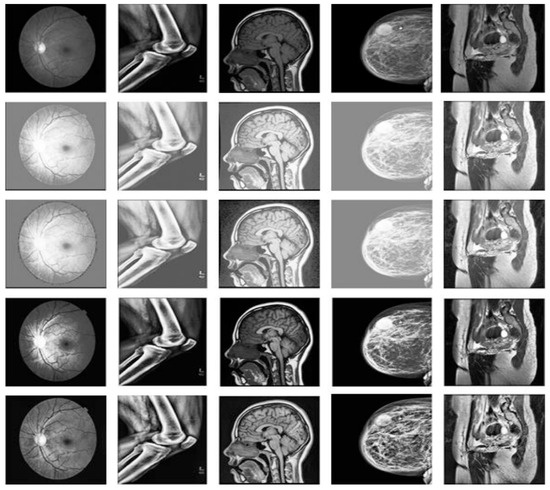

Advances in Medical Image Processing for Early Breast Cancer Detection: Classical Techniques and Deep Learning Perspectives

Breast cancer is the most common malignancy among women and a leading cause of cancer-related mortality, making early and accurate detection essential. This review summarises advances in breast imaging and computational diagnostics across mammography, ultrasound, and magnetic resonance imaging (MRI), highlighting challenges in [...] Read more.

Breast cancer is the most common malignancy among women and a leading cause of cancer-related mortality, making early and accurate detection essential. This review summarises advances in breast imaging and computational diagnostics across mammography, ultrasound, and magnetic resonance imaging (MRI), highlighting challenges in differentiating benign from malignant lesions and identifying rarer tumour types. Key preprocessing steps—denoising, deblurring, and contrast enhancement—are reviewed as they improve image quality prior to analysis. Classical methods (e.g., thresholding, edge detection, and region growing) are compared with deep learning approaches for segmentation and classification. CNNs, RNNs, and emerging transformer-based models consistently outperform handcrafted pipelines, with representative studies reporting 5–15% gains in AUC/accuracy and deep models achieving AUC > 0.85–0.95 on several benchmarks. The review also discusses dataset constraints, common evaluation metrics (AUC, Dice, sensitivity, specificity), and clinical translation barriers such as interpretability and domain shift. Overall, AI-driven methods show strong potential to enhance early detection and support improved breast cancer outcomes. Full article

Show Figures

Figure 1